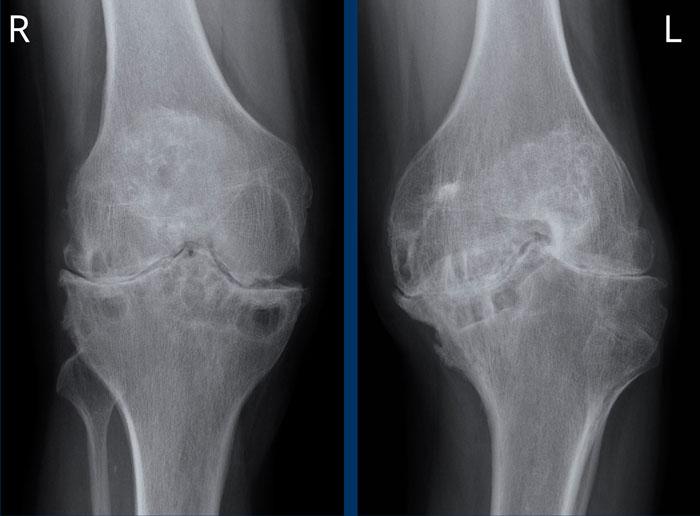

Điểm giảng dạy: khi hình ảnh tổn thương giống viêm khớp thoái hóa nhưng có biểu hiện hoặc phân bố bất thường, cần nghĩ đến bệnh khớp do hemophilia.

Bệnh nhân này có tiền sử hemophilia và tràn máu khớp tái phát nhiều lần.

Giãn túi cùng trên xương bánh chè của khớp gối phải do tràn máu khớp (mũi tên đen).

Hẹp khe khớp phía trong do phá hủy sụn và viêm khớp thoái hóa thứ phát (mũi tên trắng).

Hình thành nang xương dưới sụn phía dưới gai liên lồi cầu.

Không có hình ảnh bào mòn xương.

Hình ảnh

Hình ảnh khớp gối phải cho thấy hẹp khe khớp, hình thành nang xương dưới sụn và bào mòn mâm chày trong và ngoài.

Khớp gối trái bình thường để so sánh.

Bệnh nhân này có tiền sử lâu dài tràn máu khớp tái phát nhiều lần do hemophilia.

Hố liên lồi cầu bên trái hơi rộng, dấu hiệu này cũng có thể gặp trong viêm khớp dạng thấp thiếu niên và bệnh khớp do lao.

Lồi cầu xương đùi hình củ hành với bề mặt lồi cầu bị dẹt.

Biến dạng xương đồng tâm bên trái cũng có thể gặp trong bệnh khớp do lao.

Đây là bệnh khớp do hemophilia phân loại Arnold-Hilgartner giai đoạn V, với hẹp khe khớp nặng, hình thành nang xương dưới sụn và phá hủy xương dạng bào mòn.